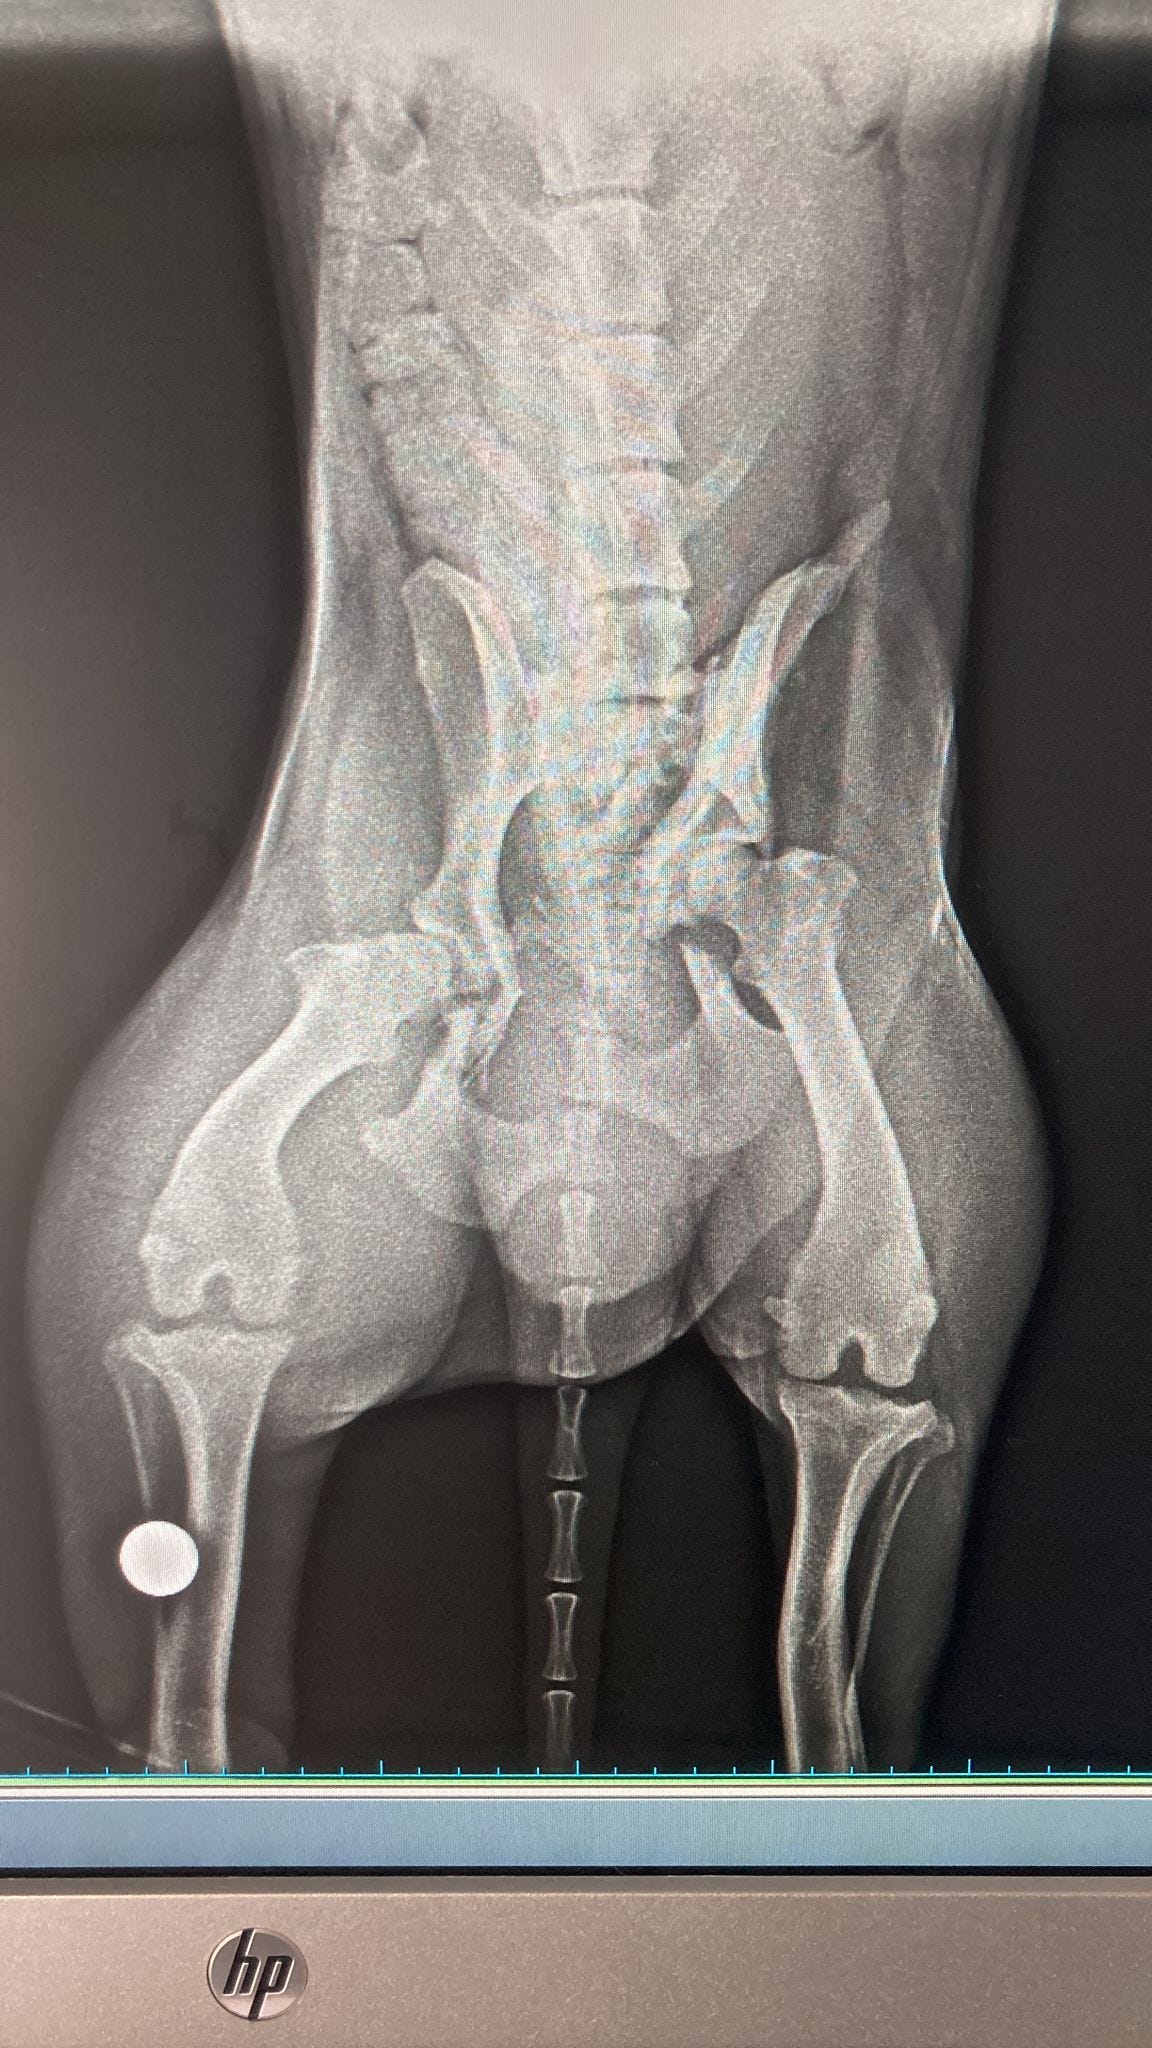

Adam’s tests revealed that he had fractures in the pelvic area & a nasty infection. The infection most likely occurring before the accident.

He also had problems emptying his bladder & bowel. His spine was undamaged so it wasn’t a spinal injury causing this. Sometimes a bullet (yes, our dogs get shot a lot) can be found near the spine which causes these kind of problems but that wasn’t the case with Adam either.

Adam was made more comfortable with a urinary catheter & pain relief. I am not going to share images of his pelvic injury as it is too distressing.